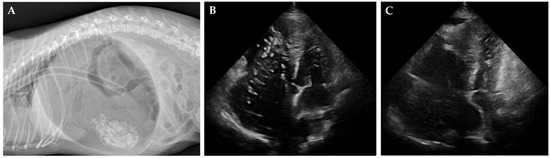

The HW and GD groups consisted of client-owned dogs that presented for therapeutic intervention (Figure 1). For the HW group, dogs included various breeds such as Poodle, Yorkshire Terrier mix, Pit Bull Terrier, and mixed-breed dogs (age range: 2–12 years; body weight: 3.72–46.0 kg). Patient selection was based on the American Heartworm Society (AHS) guideline criteria, specifically targeting dogs for whom surgical heartworm extraction was indicated due to significant worm burden or right atrial involvement as determined by echocardiography. All HW cases presented with moderate to severe heartworm disease, characterized by multiple adult worms visualized within the pulmonary arteries and/or right heart chambers. Mild clinical signs such as intermittent coughing, mild exercise intolerance, and mild ascites were observed in some cases. While none of the HW dogs in this study had developed caval syndrome at the time of intervention, we recognize the importance of including such cases to fully capture the severe end of the disease spectrum. All dogs exhibited mild to moderate pulmonary hypertension on echocardiography without evidence of severe right ventricular dysfunction or overt right-sided heart failure.

For the GD group, dogs included Dachshund, Samoyed, and Welsh Corgi breeds (age range: 1–8 years; body weight: 6.62–23.5 kg). Diagnosis of acute gastric dilatation was made based on physical examination, a detailed history, and confirmation with abdominal radiographs. Clinical signs included abdominal distension, non-productive retching, and varying degrees of cardiovascular compromise. Based on clinical assessment at presentation, one dog was classified as having severe cardiovascular compromise (poor pulse quality and prolonged capillary refill time), two dogs exhibited moderate compromise, and one showed mild cardiovascular effects. Emergency stabilization, including orogastric decompression and/or surgical intervention, was promptly performed. In all GD cases, ICG monitoring was conducted after initial stabilization to minimize the effects of acute hemodynamic instability on measurement reliability.

All NC dogs successfully underwent the procedures without complications and recovered uneventfully from anesthesia without any adverse effects. In the HW group, post-procedural echocardiographic examination confirmed a reduction in heartworm burden, allowing the dogs to proceed with the standard heartworm treatment protocol [24]. Representative radiographic and echocardiographic findings for diseased dogs (HW and GD groups) are shown (Figure 1). In the GD group, all dogs were hospitalized for continuous monitoring after decompression, with no recurrence of GD observed. The average hospitalization period was 5.75 ± 0.63 days, and at the three-month follow-up examination, no abnormalities were detected, confirming successful long-term recovery. There were no significant differences in age, weight, or gender distribution between the three groups.

Figure 1. Radiographic and echocardiographic findings in cases of gastric dilatation and heartworm disease. (A) Lateral radiograph of a dog with severe gastric dilatation, showing a markedly distended, gas-filled stomach. An orogastric tube for decompression is visible. (B,C) Right parasternal short-axis echocardiographic images before (B) and after (C) heartworm removal. Heartworms appear as short, segmented, parallel echogenic structures (B), which are no longer visible post-extraction (C).